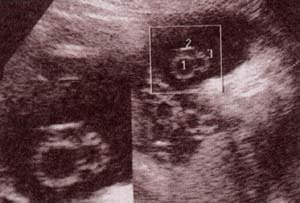

Diagnóstico Prenatal -  bolsa escrotal y su contenido Diagnóstico Prenatal -  30 semanas. se observan los testículos

fig. 51.– (a). bolsa escrotal y su contenido. 25 semanas. fig. 51.– (b). 30 semanas. se observan los testículos en un corte perpendicular al polo pélvico.

Diagnóstico Prenatal -  34 semanas. Diagnóstico Prenatal -  38 semanas. al final del tercer trimestre

fig. 51.– (c). 34 semanas. fig. 51.– (d). 38 semanas. al final del tercer trimestre es frecuente observar líquido en el escroto en escasa a moderada cantidad que corresponde al hidrocele fisiológico.